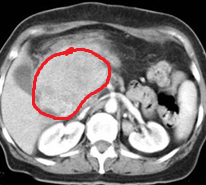

Abdominal CT scan. Hemorrhagic rupture of a simple hepatic cyst without active hemorrhage. The presence of free intraperitoneal fluid is noted (Courtesy Dr. V. Penopoulos)